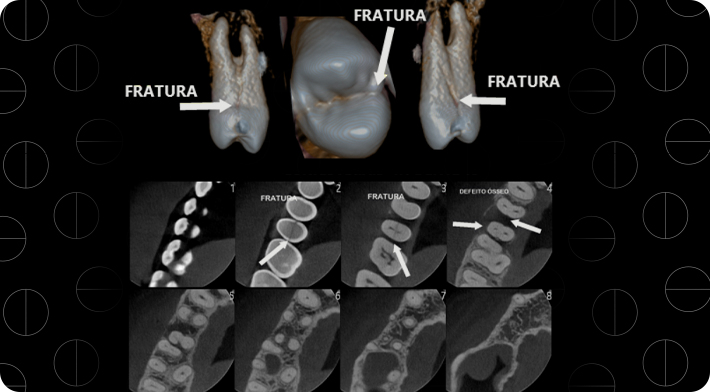

Radiologia em foco: Diagnóstico eficiente para fratura dentária

Escolher a clínica de radiologia certa, faz toda diferença no sucesso de seus diagnósticos.